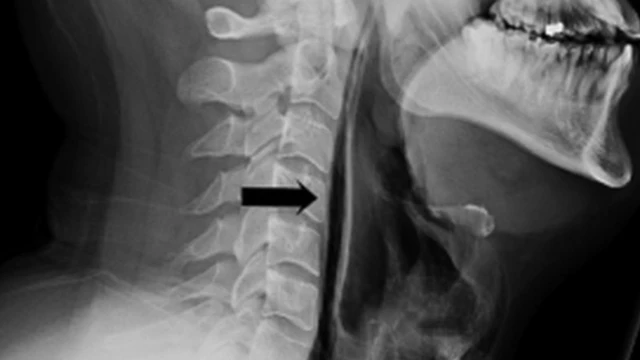

ছবির উৎস, বিএমজে

ডাক্তারের কাছে গেলে তারা পরীক্ষা করে দেখতে পান তার গলা এবং ঘাড় ফুলে গেছে, টিস্যুগুলো স্পর্শকাতর হয়ে গেছে।

এক্সরে ছবিতে দেখা যায়, তার শ্বাসনালী ফেটে গেছে এবং শ্বাস নেবার সময় তা দিয়ে বাতাস বেরিয়ে তার গলার নরম পেশীতে এসে লাগছে।